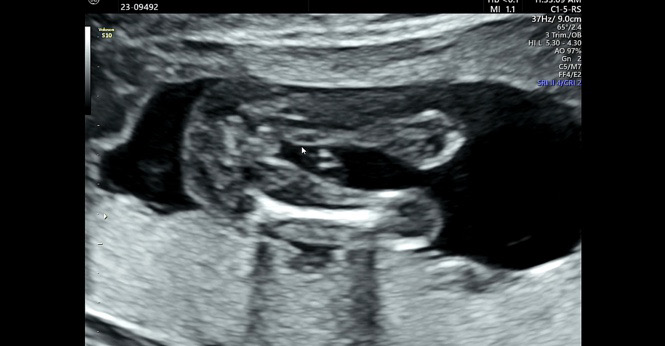

16주 사진인데 딸인데도 튀어 나와보일 수있나욤 ㅠ

아들일까요?딸일까요?

성별 궁금해요 ㅠ 알려주세욤